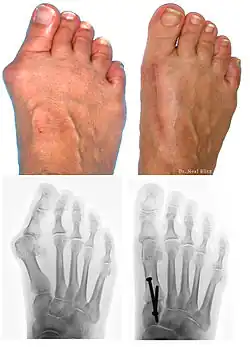

A bunion, also known as hallux valgus, is an outward deformity of the foot's metatarsophalangeal (MTP) joint which connects the big toe to the foot.[2] The rear tarsametatarsal joint that holds the metatarsal bone in a straight-ahead position weakens, the metatarsal moves outward plus rotates 90 degrees bringing the sesamoids up against the adjacent toe. This results in the head of the metatarsal bulging outward, and the big toe then bends inward toward the other toes. The joint often becomes red and painful due to rubbing in a cramped shoe.[2] The onset of bunions is typically gradual.[2] Joint complications may include bursitis or arthritis.[2] A similar condition of the little toe is referred to as a bunionette.[2]

The bump itself is due to the head of the metatarsal partly due to the swollen bursal sac or an osseous (bony) anomaly on the metatarsophalangeal joint. The larger part of the bump is a normal part of the head of the first metatarsal bone that has tilted sideways to stick out at its distal (far) end (metatarsus primus varus).

Bunions are commonly associated with a deviated position of the big toe toward the second toe, and the deviation in the angle between the first and second metatarsal bones of the foot. The small sesamoid bones found beneath the first metatarsal (which help the flexor tendon bend the big toe downwards) may also become deviated over time as the first metatarsal bone drifts away from its normal position. Osteoarthritis of the first metatarsophalangeal joint, diminished or altered range of motion, and discomfort with pressure applied to the bump or with motion of the joint, may all accompany bunion development. Atop of the first metatarsal head either medially or dorso-medially, there can also arise a bursa that when inflamed (bursitis), can be the most painful aspect of the process.

Bunions can be diagnosed and analyzed with a simple x-ray, which should be taken with the weight on the foot.[10] The hallux valgus angle (HVA) is the angle between the long axes of the proximal phalanx and the first metatarsal bone of the big toe. It is considered abnormal if greater than 15–18°.[11] The following HV angles can also be used to grade the severity of hallux valgus:[12]

- Mild: 15–20°

- Moderate: 21–39°

- Severe: ≥ 40°

The intermetatarsal angle (IMA) is the angle between the longitudinal axes of the first and second metatarsal bones, and is normally less than 9°.[11] The IM angle can also grade the severity of hallux valgus as:[12]

- Mild: 9–11°

- Moderate: 12–17°

- Severe: ≥ 18°